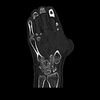

Este fantoma simula uma mão direita com duas fraturas metacarpais.

Abrange toda a mão, incluindo os dedos, metacarpo, carpo e as partes distais do cúbito e do rádio.